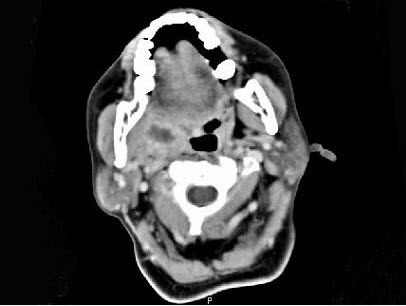

女,52岁,咽喉部疼痛半个月,伴低热,CT如图所示,可能诊断为()。

A、咽旁脓肿

B、咽部神经鞘瘤

C、鼻咽血管纤维瘤

D、咽旁淋巴瘤

E、咽旁转移癌

正确答案:

A